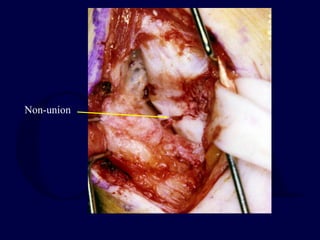

Technique: Volar ORIF

with bone graft

Exposure

โ€ข Gentle zigzag

incision directly over

the course of the

flexor carpi radialis

tendon

FCR TENDON:

stay on radial

side

Non-union

Fibrous non-union

removed

Iliac crest graft placed into

defect